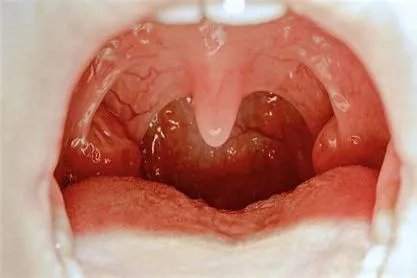

幼儿急疹表现的图片2.幼儿急疹出疹初期,有时宝宝烦躁哭闹,然后发烧3-4天左右,而且是高烧。体温在39到40摄氏度以上。高热初期伴有惊厥,少数患儿会有恶心、呕吐、咳嗽、咽部及扁桃体轻度充血等精神状态,无其他症状。

扁桃体轻度充血的图片3.热度退了,就会出现皮疹,红色斑丘疹,直径两到五毫米不等。